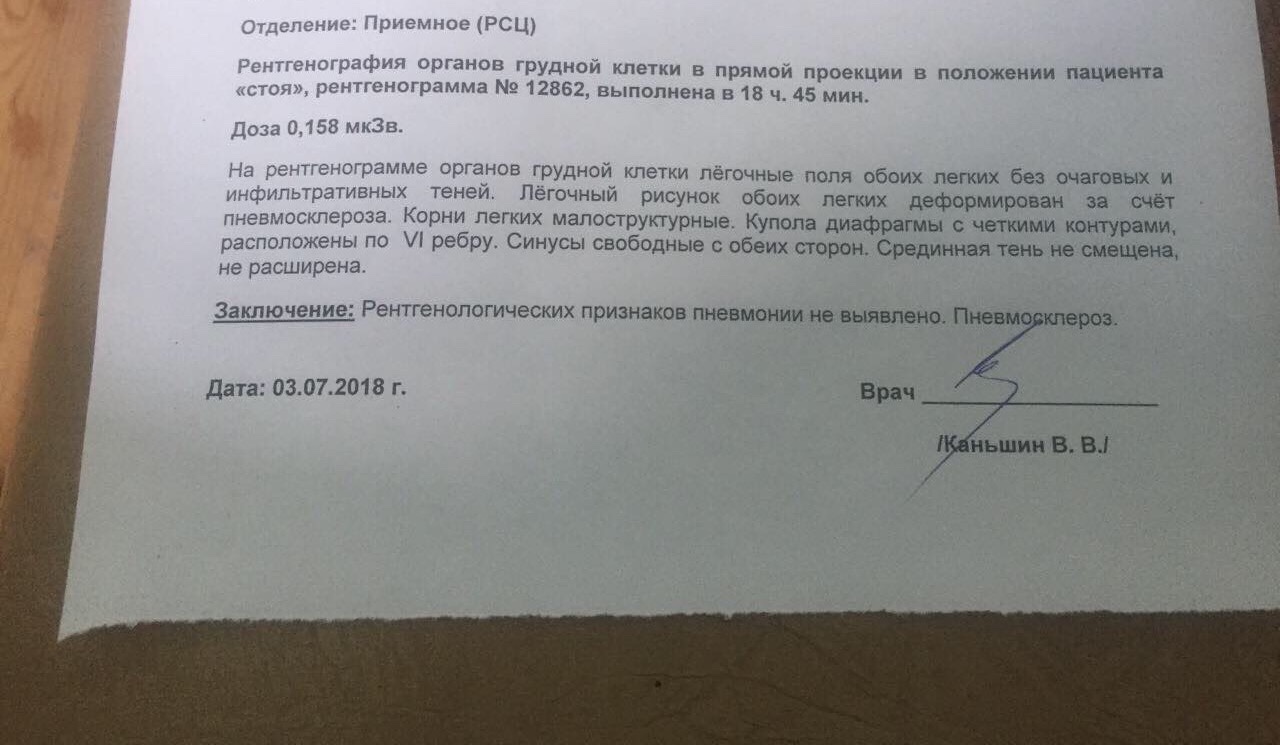

Фотографии рентгеновских снимков без необходимости направления от врача